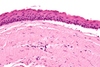

8. You perform a biopsy of a palatal lesion in an HIV+ individual. A representative microscopic image is shown below. Which of the following is true regarding this lesion? a. It is best diagnosed as Kaposi Sarcoma b. It is caused by HHV-8 c. It may also be seen in patients who are status-post organ transplant d. All of the above are true

d. All of the above are true